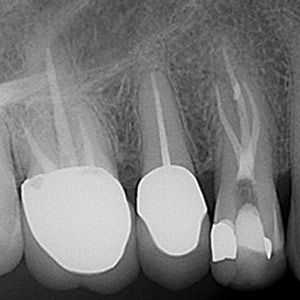

NON-SURGICAL

Oftentimes, our patients need non-surgical treatments that require minimal intervention. This intertwines with our belief that preventative maintenance and regular dental care can minimize the need for surgeries. You can rest assured that our highly trained and experienced team consistently provides the highest quality endodontic treatments and assistance available in the North Shore.